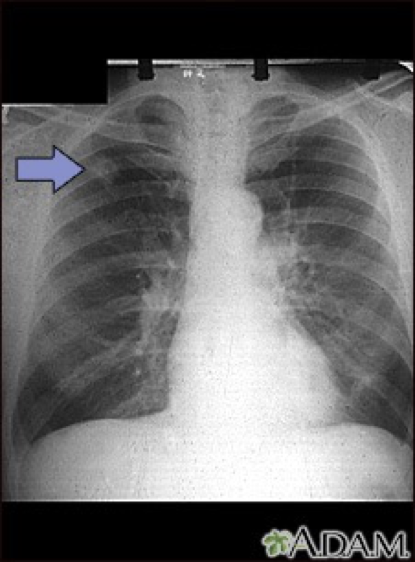

Pleural effusion with tracheal deviation